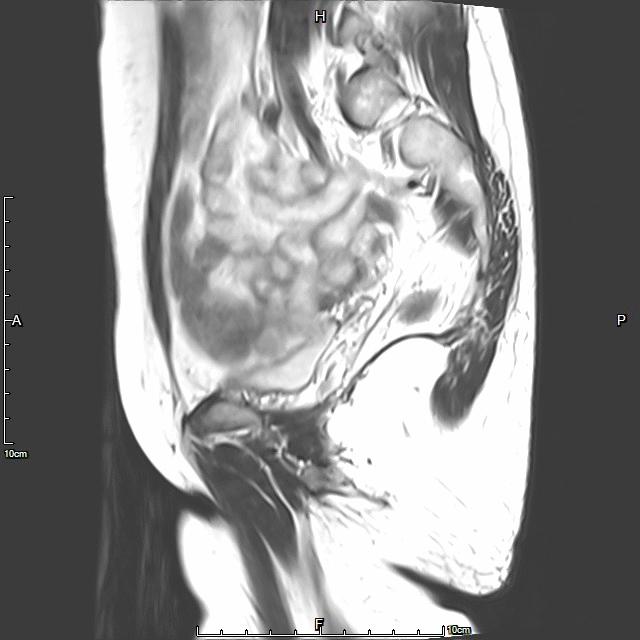

- 术前MRI检查显示子宫明显增大,弥漫型子宫腺肌症。

- 术后复查MRI显示子宫明显缩小,腺肌瘤明显坏死吸收。

例3

中年患者,发现“子宫腺肌症”10年余,近5年痛经、月经量增多等症状明显加重,导致贫血,严重影响生活质量。MRI检查显示子宫明显增大,子宫前壁明显增厚,合并粘膜下子宫肌瘤。术前诊断为子宫腺肌症合并粘膜下子宫肌瘤。